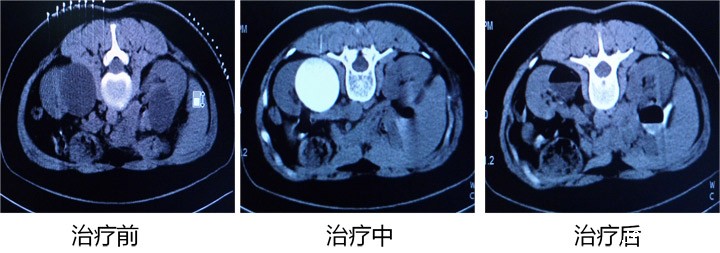

以下是成功病例的CT影像对比:

男,78岁,肝巨大囊肿,CT引导穿刺引流聚桂醇硬化术